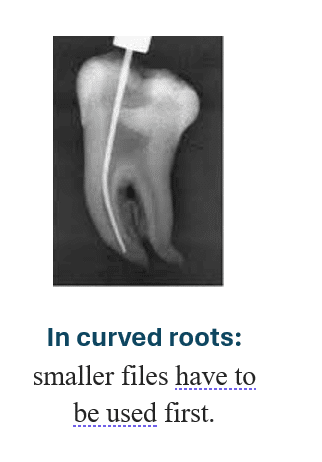

- Curved canals

Step 3 — Pre-bend small file

Use #10 K-file with sharp bend at the last 2–3 mm.

A straight file will not find the pathway.

Use gentle watch-winding movement beside the fragment.

Never apply pushing pressure.